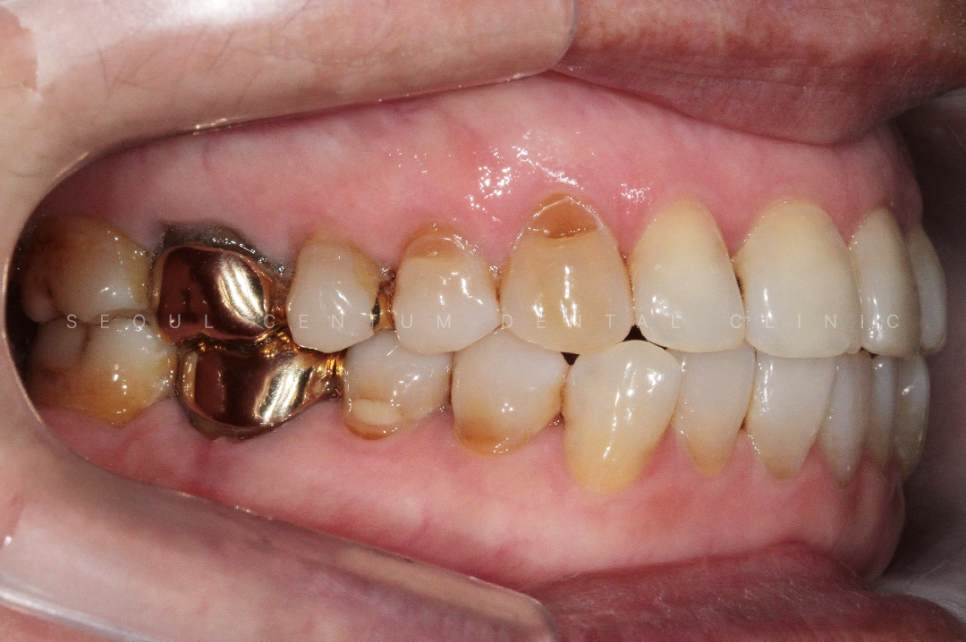

실제 육안으로 봤을 때도 크게

치경부마모증이 진행된 부분이 많았고

당일에 바로 진행을 하게 되었습니다.

크게 진행이 된 8개의 치아를 진행하기로 했고

강도가 강한 레진으로 진행해 오래

유지를 잘 해보시기로 이야기가 되어

레진으로 진행을 했습니다.